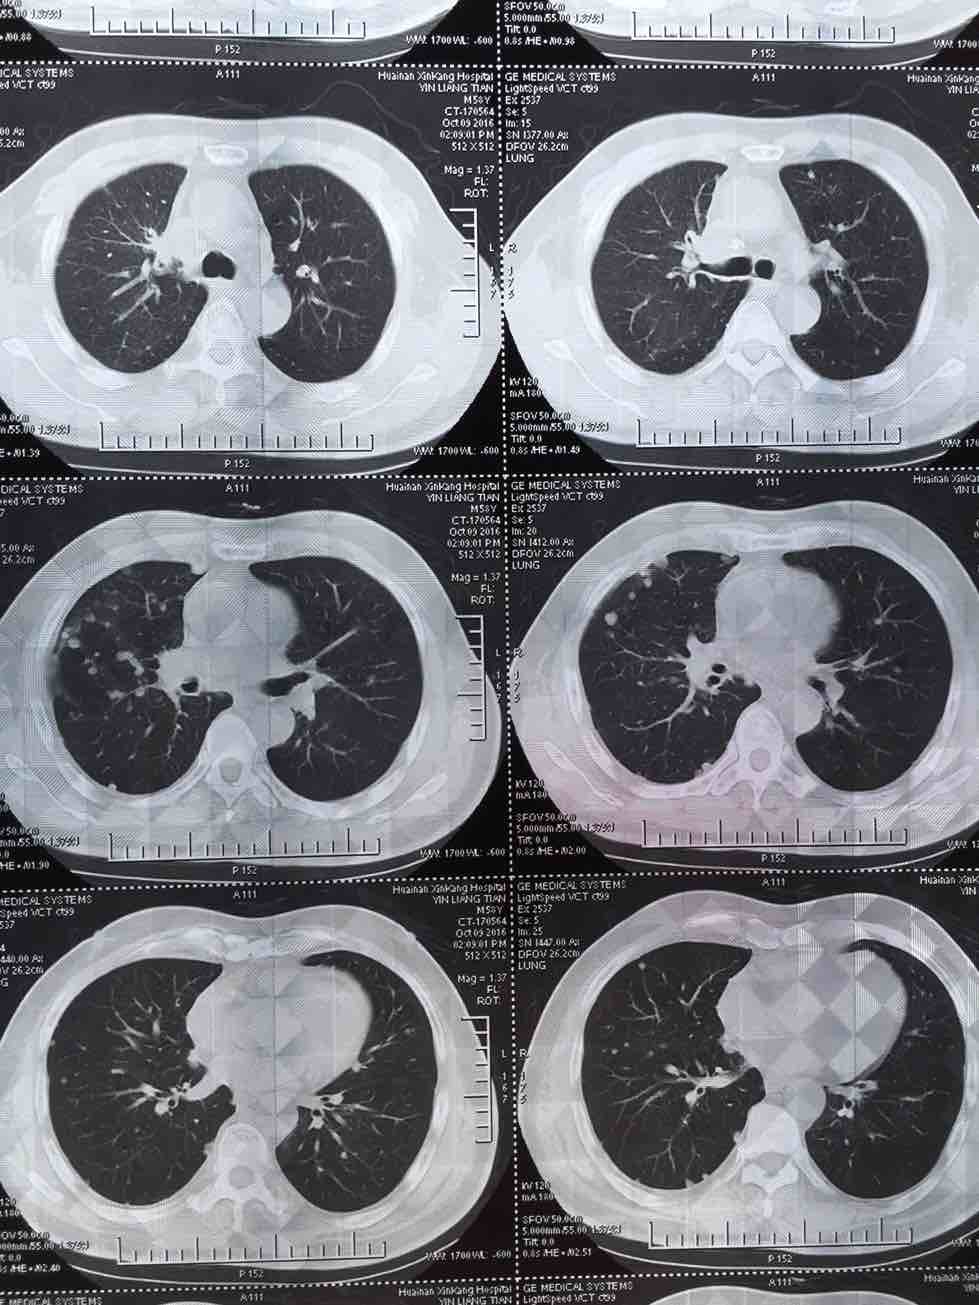

肺腺癌晚期治疗经验

我父亲今年一月份查出肺腺癌晚期伴两肺及腰椎骨盆转移,吉西他滨 顺铂两次,无效,后培美曲塞用了六次,最后一次今年7月25号出院,控制很好,期间主病兆放疗15次有所缩小,今年10月15号复查,两肺转移兆增多增大,紧接着做穿刺基因检测,结果野生型,顿时绝望,盲吃易瑞莎一个月,老天爷眷顾有效,病兆明显缩小或消失!!